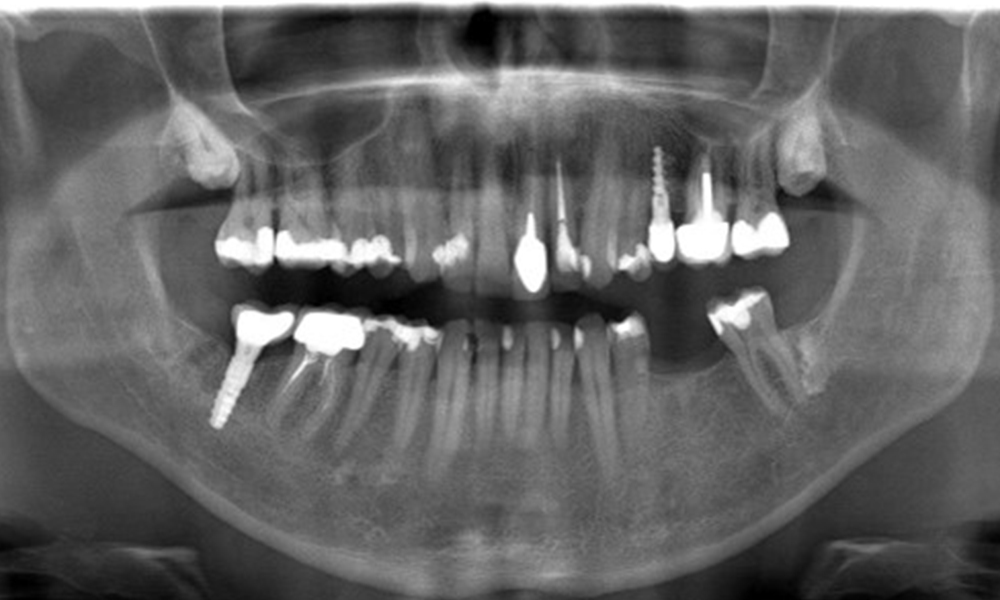

В медицинската история 55-годишният пациент заявява, че няма хронични заболявания и не приема никакви лекарства. Начинът на живот на пациента също е без забележки. Пациентът има няколко зъбни възстановявания и два импланта (2-ри и 4-ти квадрант). Въз основа на настоящите данни се установява гингивит при иначе стабилно пародонтално състояние върху редуцирания пародонт (стадий III, степен А).

Предишни лечения: зъбни възстановявания (съчетание от нескъпоценни метали и керамика), два импланта (2-ри, 4-ти квадрант)

Препоръчително лечение според IPC

Пациентът не показва особени рискови фактори със специфични дентални последици. Следователно ключовият фактор е изискването по отношение на оралното здраве. В това отношение доброто орално здраве се проявява при стабилен, редуциран пародонт. Ако при контролен преглед се установят данни за увеличаване на дълбочината при сондиране в сравнение с изходното ниво, съчетано с дифузно кървене, следва да се предприеме диагностика с помощта на рентгенова снимка (дентален рентген), за да се установи загуба на периимплантатна кост на ранен етап и да се предприемат съответните интервенции.